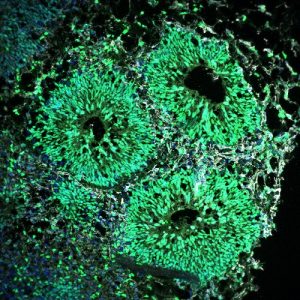

Mehr erfahren zu: "Kleines Molekül – Großes Potenzial für die Gentherapie" Kleines Molekül – Großes Potenzial für die Gentherapie Tübinger Forschende beheben einen Gendefekt in der Petrischale und kommen damit einer Gentherapie der Spinozerebellären Ataxie Typ 3 einen Schritt näher.